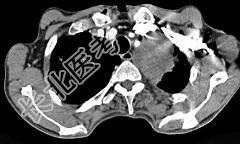

- 单项选择题56岁,男, 意识错乱情绪不稳定一周,请结合胸片和CT, 选出最可能的诊断 ( )

A、肺癌

B、错构瘤

C、胸内甲状腺肿

D、韦格肉芽肿

E、胸腺瘤